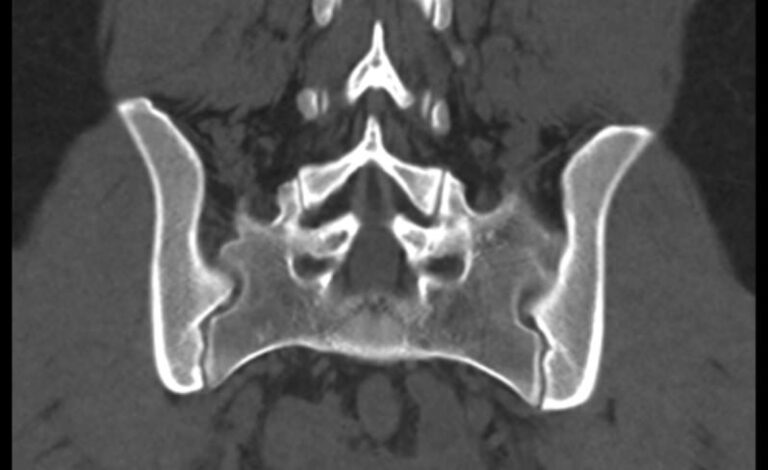

Мультиспиральная компьютерная томография – это современный наиболее достоверный метод диагностики различной патологии крестцово-копчикового сочленения, основанный на послойном сканировании органов и тканей с использованием рентгеновских лучей. Благодаря получаемым тонким срезам с шагом от 0,5 мм и последующей обработке данных компьютерными программами удается получить изображения костных структур, связочного аппарата, межпозвоночных дисков и окружающих тканей. В дальнейшем данные могут быть преобразованы в 3D-изображения исследуемой анатомической области. Это позволяет выявлять различные заболевания позвоночника на ранних стадиях и назначать своевременное лечение.

КТ крестцово-копчиковой области может выявить наличие следующих патологий:

- вывихи в крестцово-копчиковом сочленении;

- остеохондроз;

- септическую, туберкулезную или метастатическую деструкцию крестца;

- остеопороз (визуальная оценка);

- Смещение или перелом позвонков, а также оценить локализацию отломков позвонков;

- гематомы в области поврежденной области;

- воспалительные процессы;

- новообразования и метастазы;

- последствия травм и операций;

- дегенеративно-дистрофические изменения.